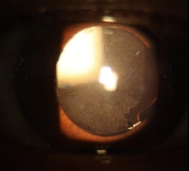

<반짝거리는 인공수정체 뒤로 희뿌연 혼탁이 보이는 후발백내장>

앗, 후발백내장이다!!!